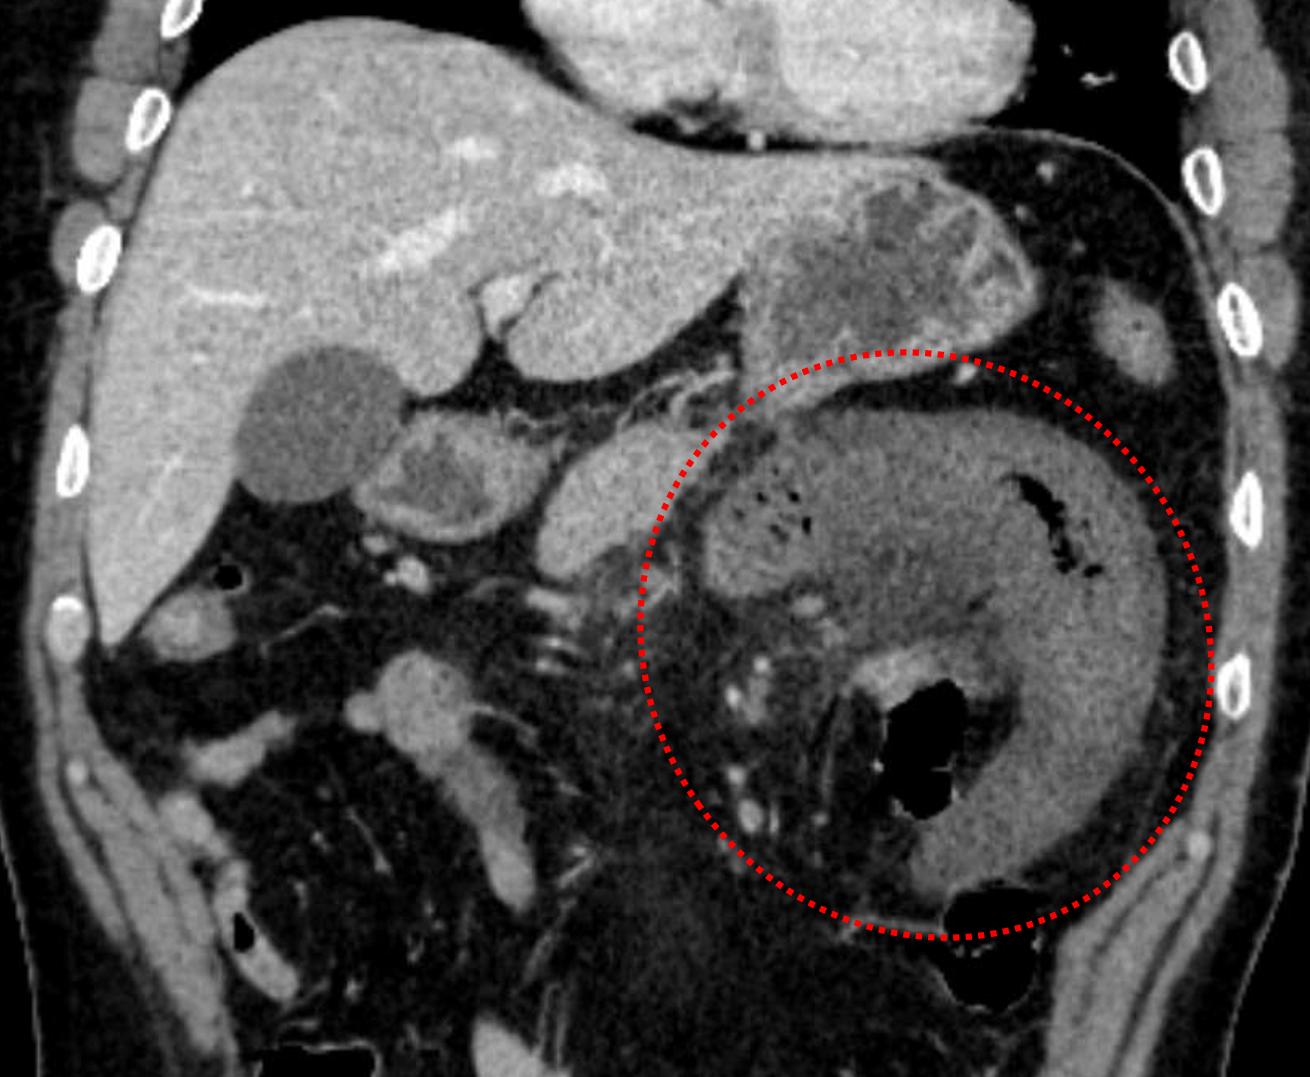

Sample ReportFindings concerning for developing segmental ischemia involving the proximal jejunum secondary to SMV thrombosis. Nonocclusive thrombus also extends slightly into the main portal vein. No pneumatosis, portal venous gas, or pneumoperitoneum.